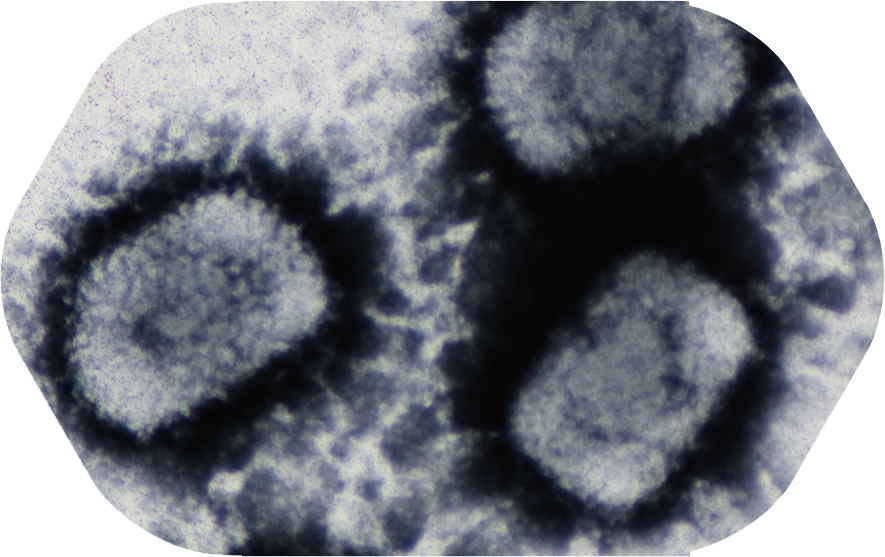

显微镜下的牛痘病毒